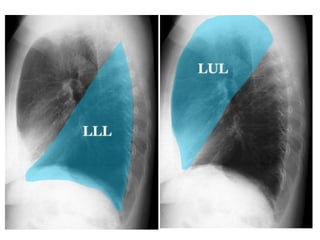

Lateral Film

Left Lateral

Right Lateral